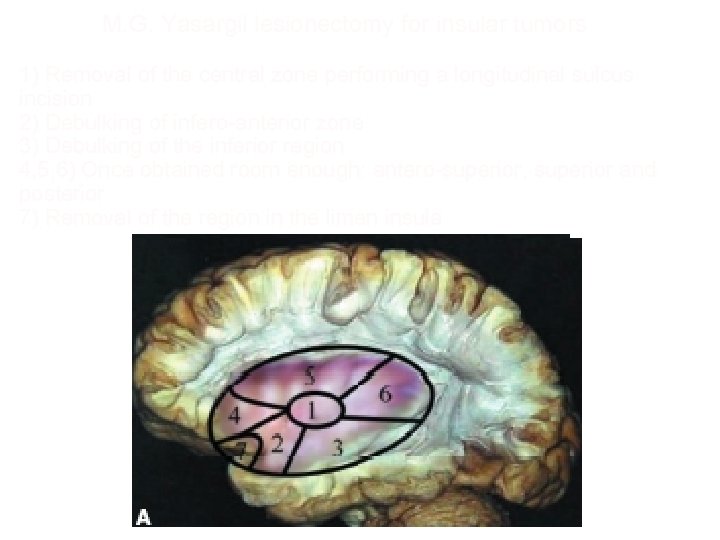

M. G. Yasargil lesionectomy for insular tumors 1) Removal of the central zone performing a longitudinal sulcus incision 2) Debulking of infero-anterior zone 3) Debulking of the inferior region 4, 5, 6) Once obtained room enough: antero-superior, superior and posterior 7) Removal of the region in the limen insula